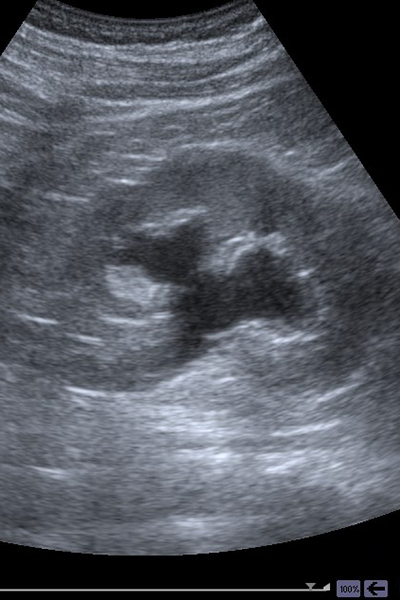

超音波検査は、超音波を出力するプローブを体に当て、跳ね返ってきた反射波によってリアルタイムに体内の状態を見る検査です。仰向けに寝た状態で検査する箇所にゼリーを塗り、その上から探触子をあて観察します。

腹部だけでなく、乳腺、甲状腺、体表臓器など幅広い部位の検査に用いられます。医療用に用いられる超音波は骨や空気には伝わらないので、骨と肺の検査はできません。